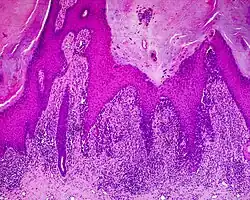

Histology

The main characteristic of acral lentiginous melanoma is continuous proliferation of atypical melanocytes at the dermoepidermal junction.[23] Other histological signs of acral lentiginous melanoma include dermal invasion and desmoplasia.[24] This invasion usually occurs many years after the initial lesion first appears.[7]

According to Scolyer et al.,[25] ALM "is usually characterized in its earliest recognisable form as single atypical melanocytes scattered along the junctional epidermal layer".